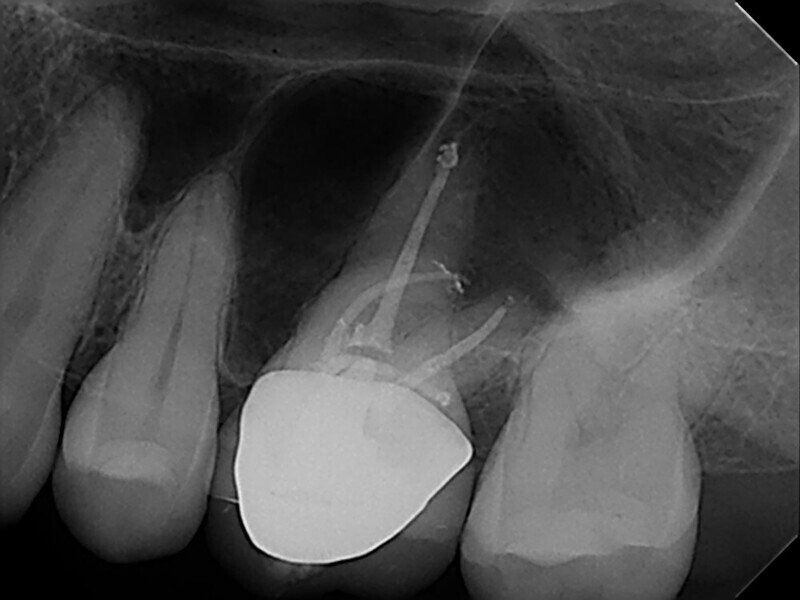

EdgeFile X7: Beastly bifurcation